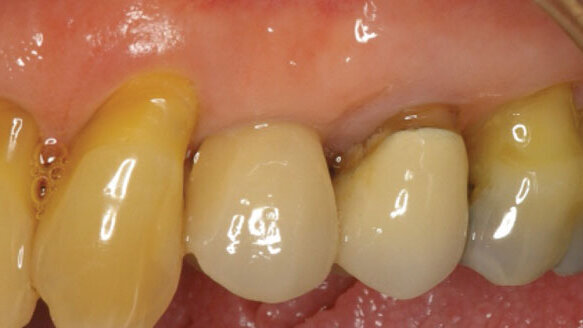

Gingival level and height was symmetrically preserved, enabling oral hygiene to be maintained while creating an esthetic blending with the lateral surrounding area. There was no depression nor any noticeable differences with the adjacent areas. The gingiva on the adjacent teeth, however, had receded, exposing some dentin on the periodontally compromised teeth lateral to the implant. There is no probing depth on the implant. It is and has been the same for nine years since insertion.

Figure 10 shows the gingival tissue and its height being maintained, enabling the pinkish-white keratinized tissue to blend laterally with the gingival tissue of the natural adjacent teeth. The implant has been hygienically maintained. There is no depression nor any defect of the implant-gingival tissue. The implant is a success in esthetic appearance, health and function.